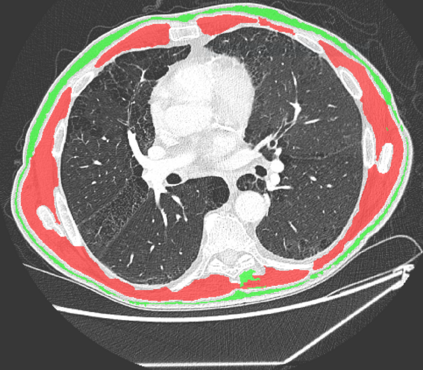

The COVID-19 pandemic has had a considerable impact on day-to-day life. Tackling the disease by providing the necessary resources to the affected is of paramount importance. However, estimation of the required resources is not a trivial task given the number of factors which determine the requirement. This issue can be addressed by predicting the probability that an infected patient requires Intensive Care Unit (ICU) support and the importance of each of the factors that influence it. Moreover, to assist the doctors in determining the patients at high risk of fatality, the probability of death is also calculated. For determining both the patient outcomes (ICU admission and death), a novel methodology is proposed by combining multi-modal features, extracted from Computed Tomography (CT) scans and Electronic Health Record (EHR) data. Deep learning models are leveraged to extract quantitative features from CT scans. These features combined with those directly read from the EHR database are fed into machine learning models to eventually output the probabilities of patient outcomes. This work demonstrates both the ability to apply a broad set of deep learning methods for general quantification of Chest CT scans and the ability to link these quantitative metrics to patient outcomes. The effectiveness of the proposed method is shown by testing it on an internally curated dataset, achieving a mean area under Receiver operating characteristic curve (AUC) of 0.77 on ICU admission prediction and a mean AUC of 0.73 on death prediction using the best performing classifiers.